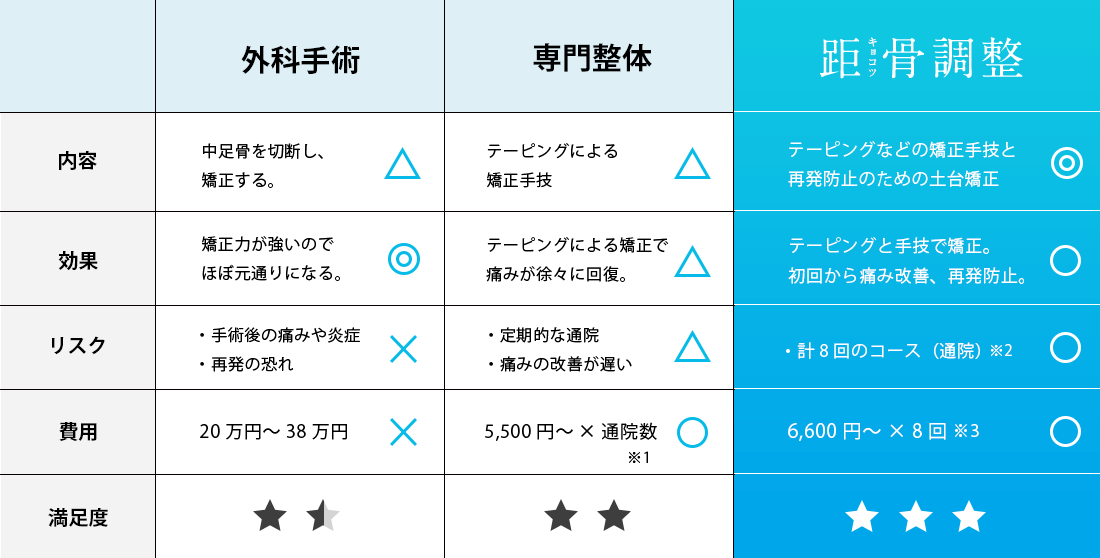

志水式整体では、人間の土台である「骨盤」と「足元(距骨)」をセットに考え、整えることにより、重力に負けない対応力を取り戻す「究極の土台調整」を行っております。

慢性的な膝や腰の痛み、頭痛、肩こり、外反母趾、骨盤の歪み、婦人科系疾患、慢性疲労、不眠、カラダのたるみ、便秘と多様な悩みに苦しむ方をこれまで施術してきましたが、どの方も共通していたのは「距骨」が歪んでいたことでした。 日常的な様々な痛みや症状の原因は、この土台である距骨にあるのです。

距骨を整える事により痛みの無い健康なカラダを取り戻して行きます。